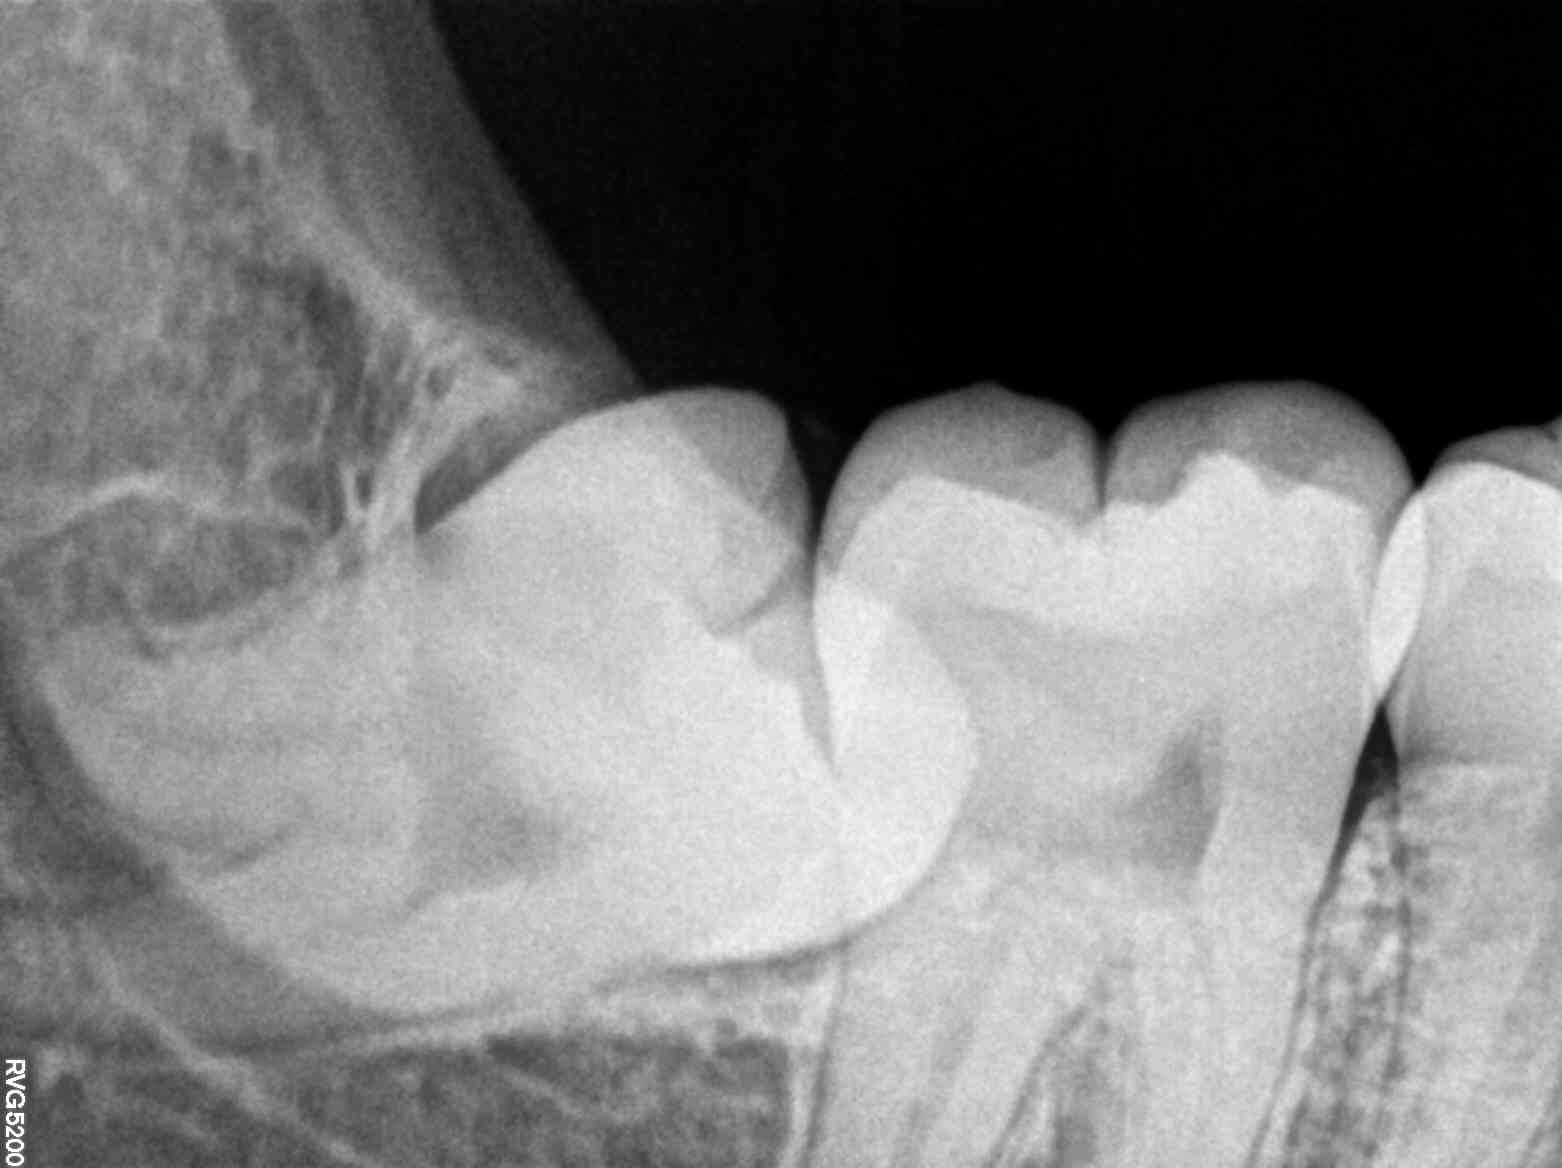

The advanced X-ray services offered at the clinic provided a comprehensive look at Riya’s dental structure that traditional examination methods could not. These X-rays offer high-resolution images that reveal even the most subtle dental anomalies, helping dentists to diagnose issues with precision.

For Riya, this technology uncovered a hidden dental cavity that was the root cause of her discomfort. The X-ray images detailed the exact location and extent of the damage, allowing the dentist to propose a targeted treatment plan that addressed the problem effectively.